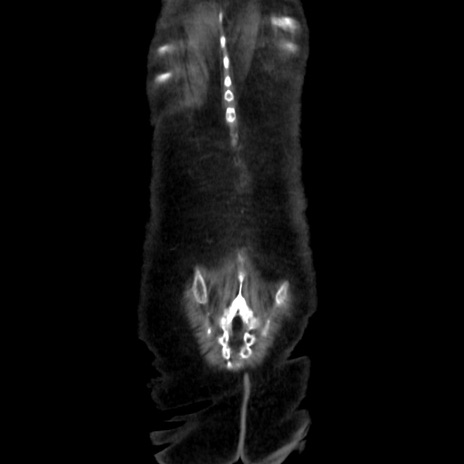

症例40(冠状断像)

冠状断像